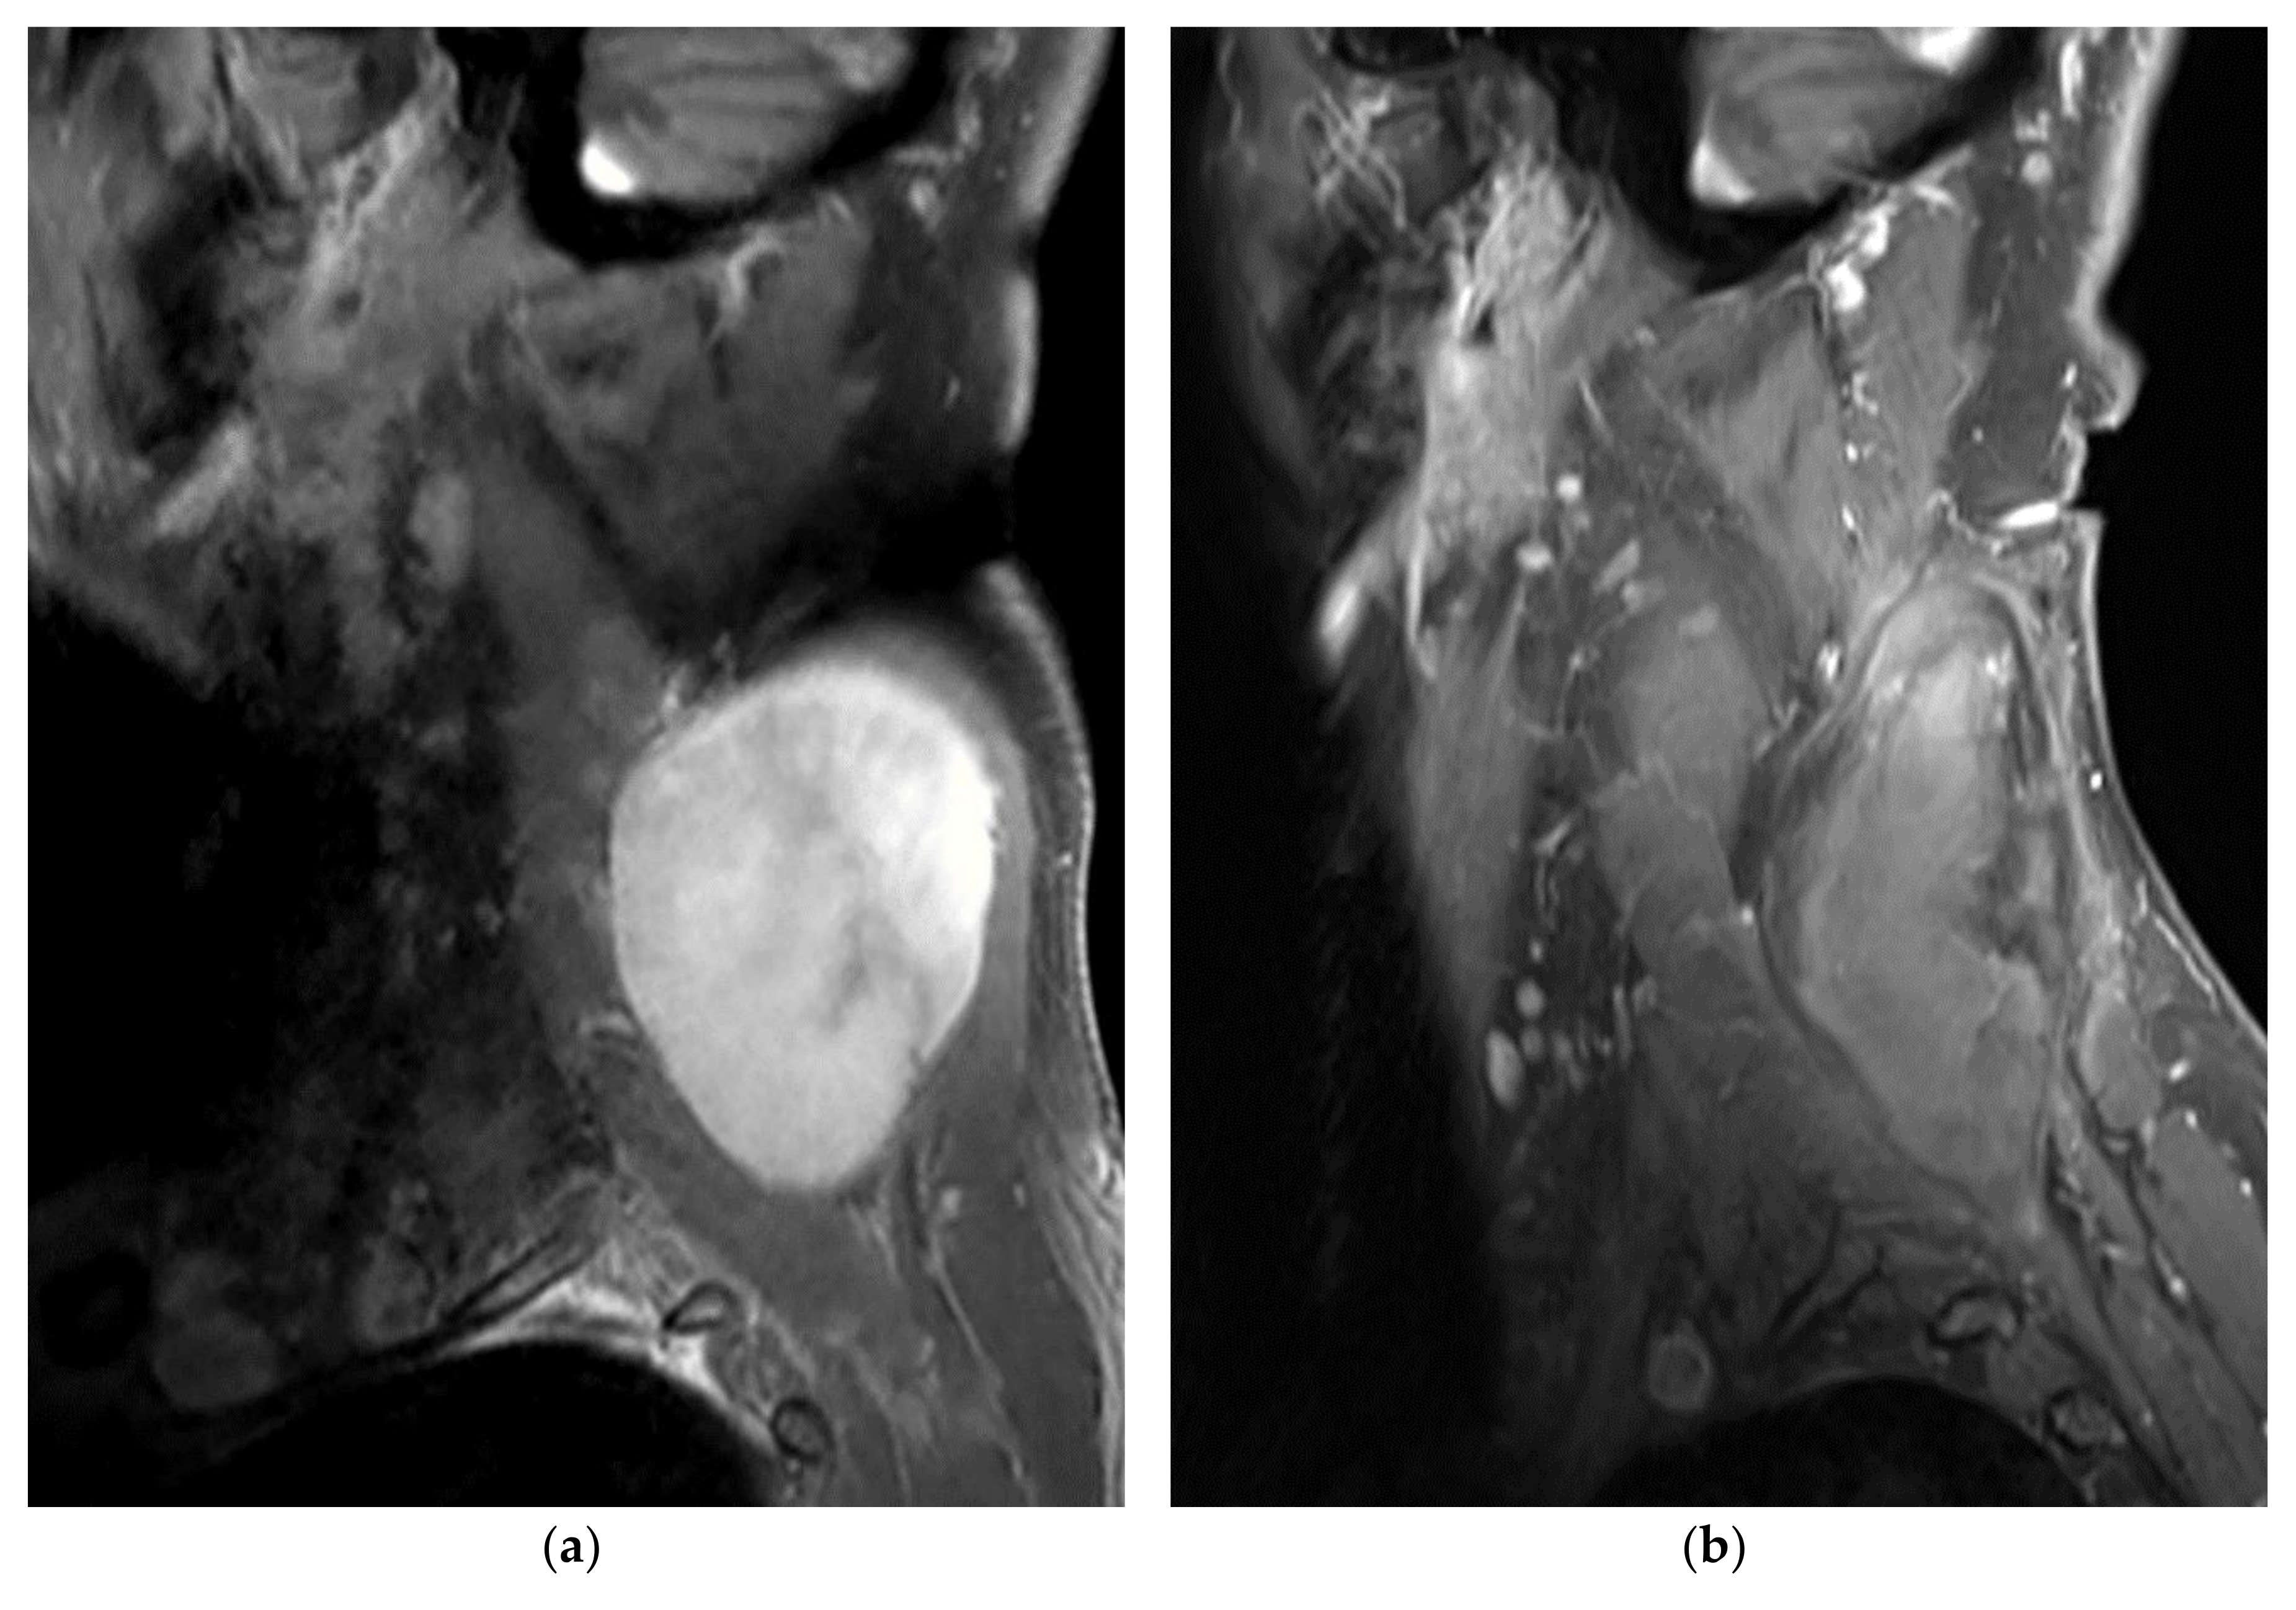

In the surgical theater, the surgeon performed tissue dissection around the DT in order to achieve adequate exposure of the surgical field and surrounding neurovascular structures (Figure 2). The cryoprobes were then positioned inside the tumor under US guidance. The two freeze-cycle CA protocol was then applied. Ice ball monitoring was performed with both direct visualization and US. Whenever necessary, the surrounding tissues were warmed via direct warm saline instillation.

A 38-year-old female patient with EAD tumor of the left upper trunk/thoracic spine treated with open surgery CA (patient no. 7). (a) Intraoperative view of the DT (yellow outlines) with surgical exposition of the left brachial plexus (blue strings); (b) Positioning of six cryoprobes under US guidance with ice-ball formation and extension on the tumor surface.